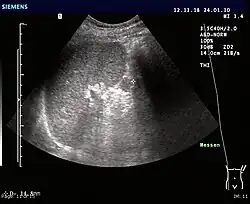

Eine Nebenmilz (Splen accessorius, Lien accessorius, Splenunculus) ist das Resultat einer häufigen embryologischen Fehlentwicklung, bei der ein oder mehrere kleine Knötchen von Milzgewebe unabhängig von der Milz, meist im Bereich des Milzhilus, im Bauchraum vorliegen. Diese Normvariante muss von der Splenose unterschieden werden, die das Resultat einer Versprengung von Milzgewebe im Rahmen einer Milzverletzung ist.[1]

Makroskopisch imponieren Nebenmilzen als rundliche, üblicherweise etwa kirschgroße, 1–1,5 cm (maximal etwa 4 cm) messende, meist von einer dünnen Kapsel begrenzte Raumforderungen von dunkelrötlicher Farbe. Sie sind ganz überwiegend im Bereich des Milzhilus (75 % der Fälle) lokalisiert, werden aber auch längs der Milzgefäße, in den gastrosplenischen oder splenorenalen Ligamenten, der Wandung von Magen und Darm, im Pankreasschwanz, dem Mesenterium sowie selten auch im Bereich des Beckens oder Skrotums gefunden. Wenige Einzelfallberichte beschreiben das Vorhandensein von Milzgewebe innerhalb des Leberparenchyms. Nebenmilzen kommen einzeln oder multipel vor, wobei ihre Zahl jedoch nur selten sechs überschreitet. Feingeweblich entspricht der Aufbau einer Nebenmilz dem der Milz, das heißt die Herde setzen sich aus einer roten und weißen Pulpa zusammen.[1]